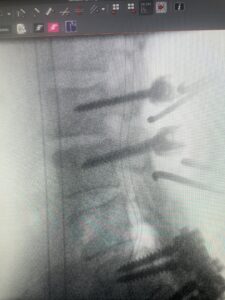

The next patient is a 54 year-old male who presents with 3 years of neck pain with associated numbness and tingling of his extremities. Patient had had physical therapy, chiropractic care, and epidural steroid injections with no significant relief. The patient on exam had weakness in a long tract distribution on the left. MRI revealed four level disc disease from C3-4 to C6-7 with a moderate kyphosis and cord compression and signal change at C3-4 (Fig. 9). Because of the kyphotic deformity it was decided to perform a four-level anterior cervical discectomy and interbody cage at each segment as well as plate. The patient had significant osteophyte disease at each level which required a high-speed drill to shave down the osteophytic disease and remove and decompress the foramina with fine Kerrison. Intraoperative imaging revealed good placement of the cages and plate at each level (Fig. 10). The patient had good relief of his preoperative symptoms.

Fig 10a and 10b: Lateral cervical x ray demonstrating placement of C3-C 7 interbody cages and plates.